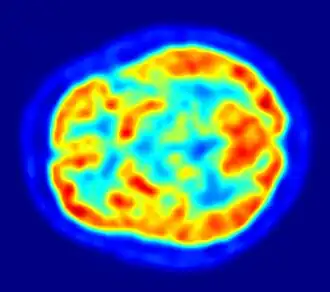

-

Imagen de resonancia magnética nuclear de una cabeza humana -

PET tomado con un ECAT Exactitud HR+